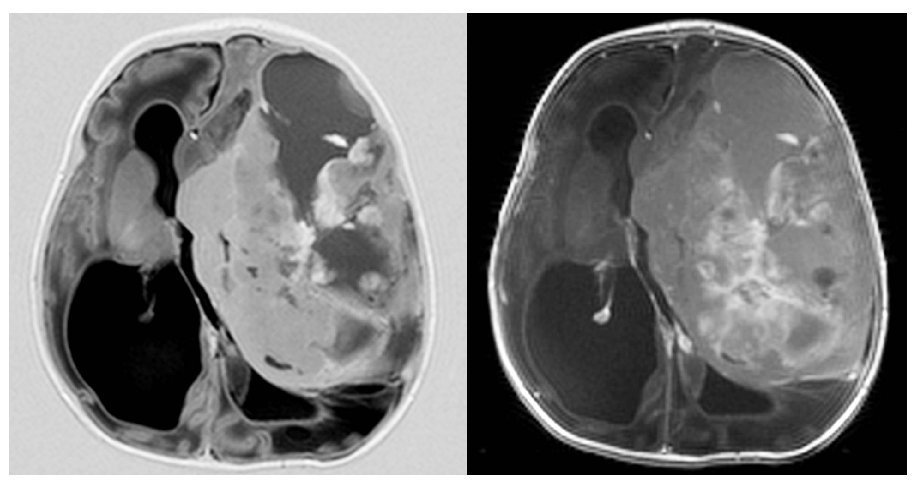

Fig. 4.